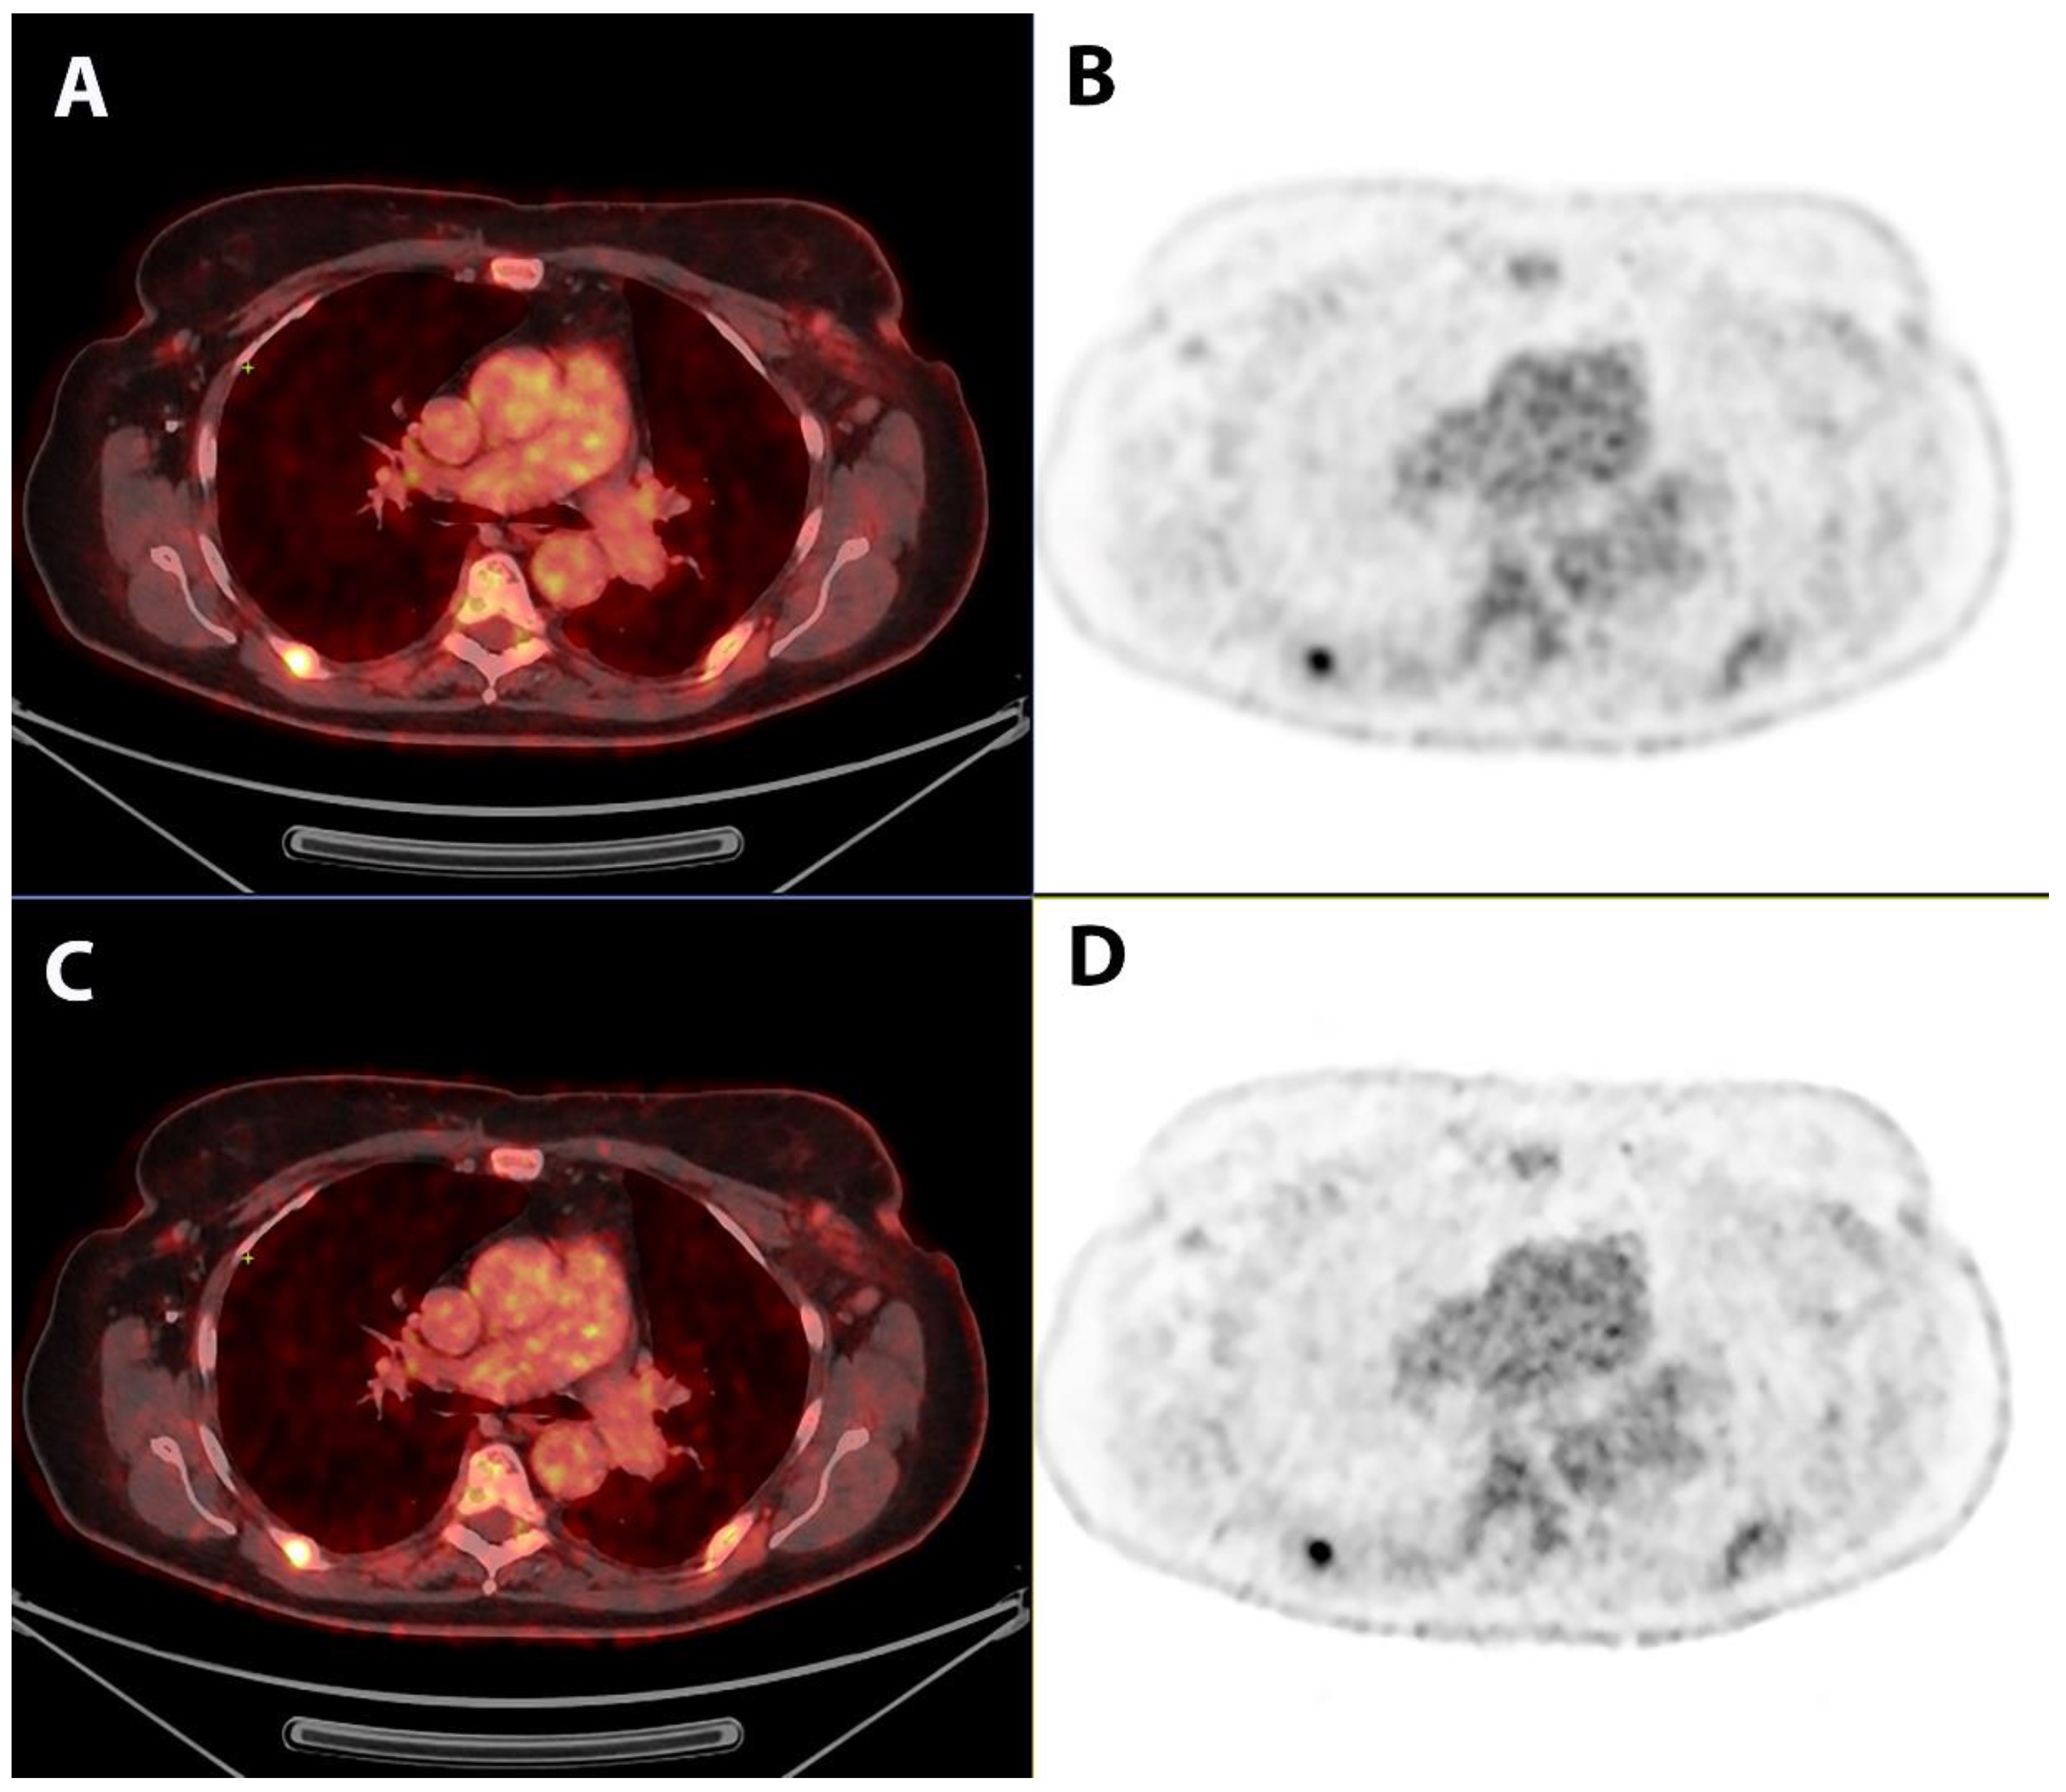

Comparison of Image Quality and Quantification Parameters between Q.Clear and OSEM Reconstruction Methods on FDG-PET/CT Images in Patients with Metastatic Breast Cancer

2. Materials and Methods

2.3. Qualitative Image Analysis

2.4. Quantitative Image Analysis

3. Results

4. Discussion